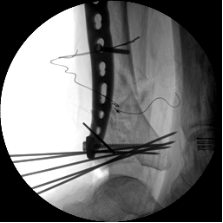

1.CO外固定半環連接跟骨穿針并通過CO接骨機器人配套的連接桿與CO接骨器人中間機械臂相連,調整機械臂,進行骨折端初步復位,C臂確認復位滿意,關節間隙拉開。

2.CO接骨機器人持續牽引維持復位,選擇前外側切口對前外側骨塊進行撬撥復位,并用克氏針進行臨時固定。C臂透視復位滿意,放置兩塊鋼板進行固定。